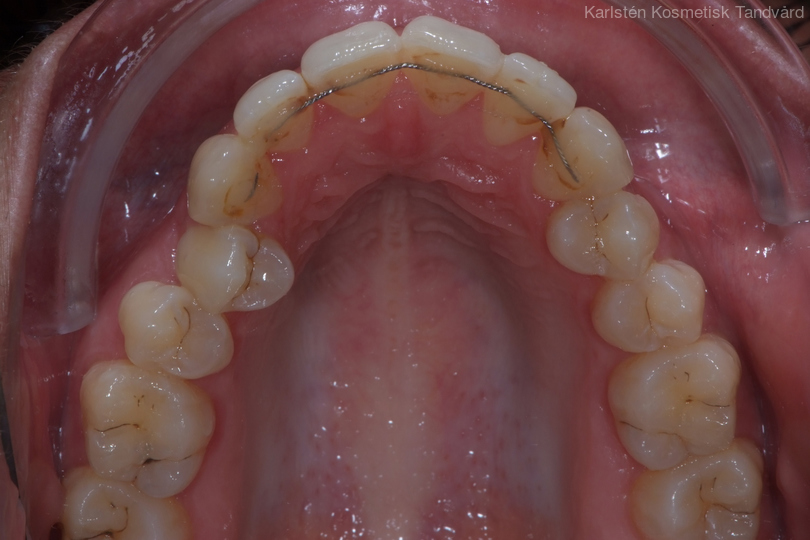

Ung kvinna som tidigare haft tandreglering. Upplever inte att tänderna står i en fin tandbåge. 11 månaders behandling med genomskinliga Invisalignskenor resulterade i ett fint leende.